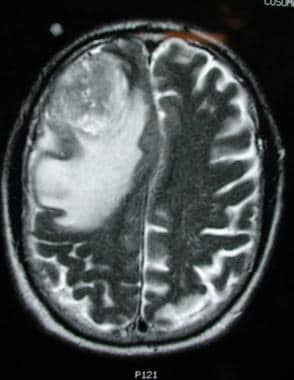

T2加权图像显示与前一图像相同的病变,有明显的水肿和中线移位。这一发现与高级别或恶性肿瘤一致。图片由马里兰州乔治·贾洛提供。